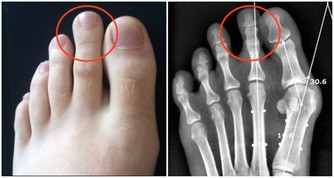

4、骨骼強壯。

中醫認為,腎主骨,骨靠腎精滋養,腎好骨才好。腎氣衰敗會出現骨質疏鬆、腰酸背痛,甚至牙齒出現鬆動。